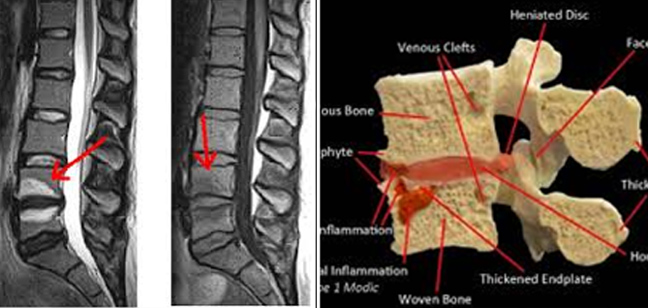

Αυτή η πίεση όταν διαρκέσει επί πολύ, αρχίζει να επιδρά στη σκληρότητα του οστού και όπως όταν το κτυπήσεις δημιουργεί οίδημα. Το οιδηματώδες αυτό κόκκαλο (οστούν) φαίνεται στην μαγνητική τομογραφία (λήψεις Τ2 και Stir) με άλλο χρώμα.

Αυτό ονομάζεται Μodic και εκφράζεται παθολογικά με βαθύ πόνο στη μέση μετά κόπωση και στο κρεβάτι στην ανάπαυση.